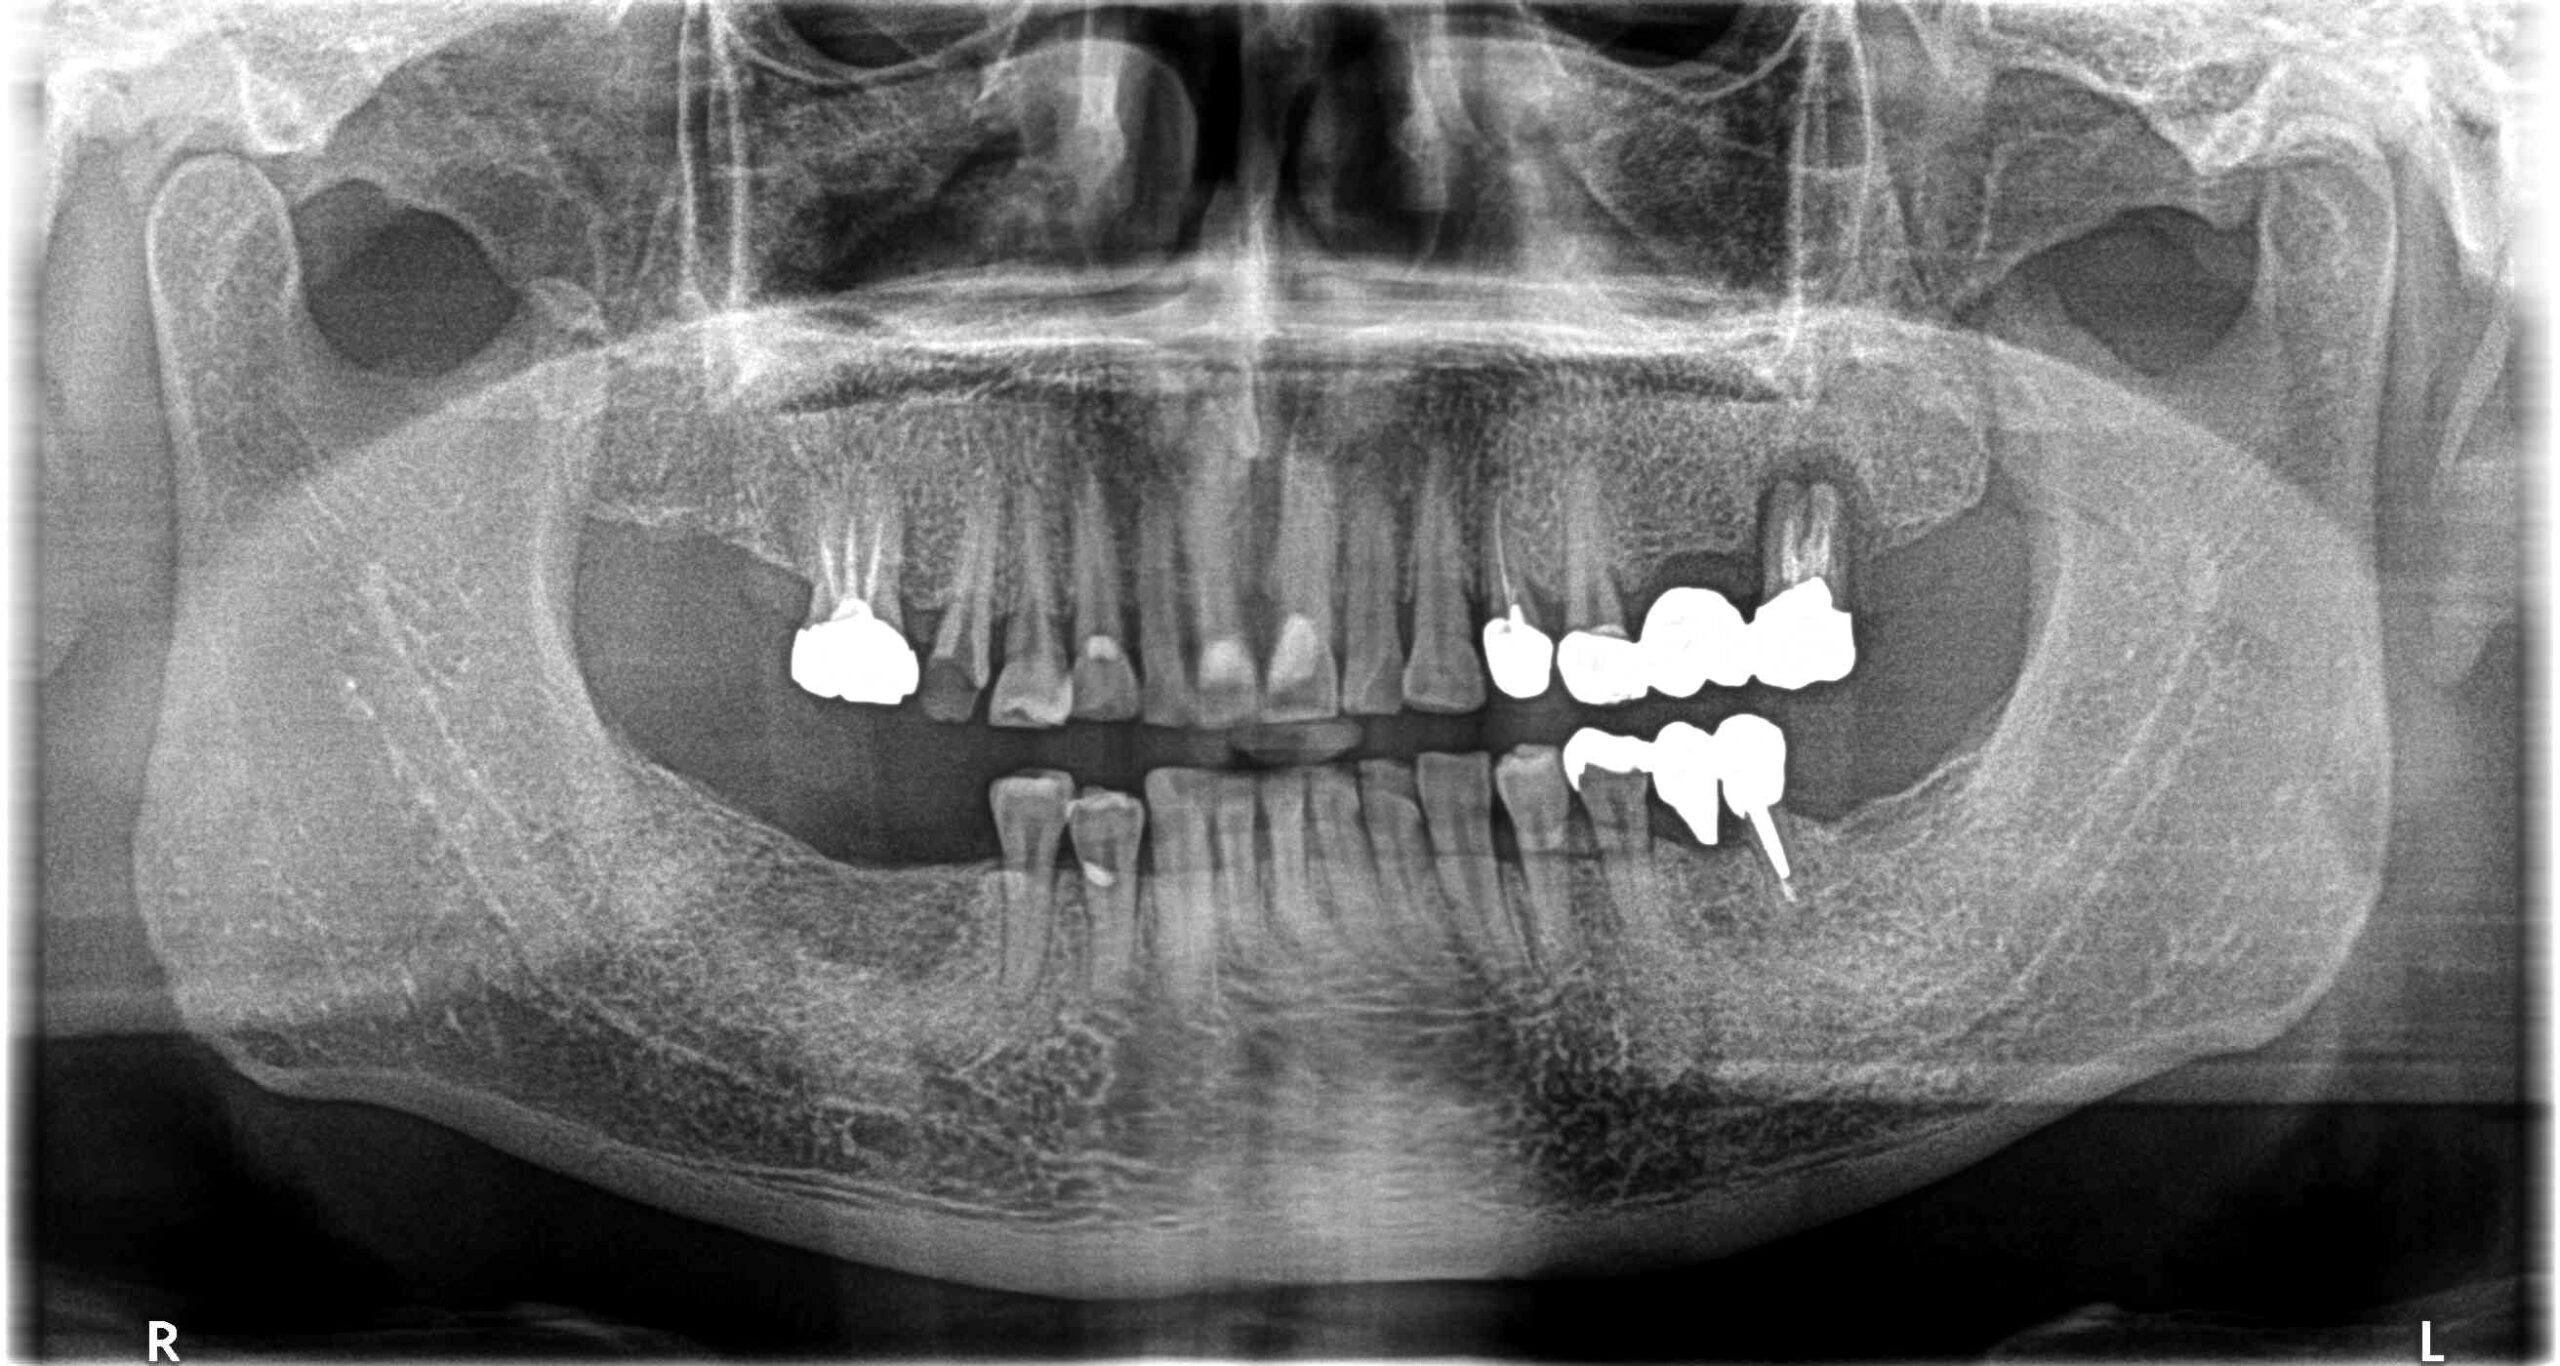

治療経過 主訴は被せ物の脱離であったが、診査の結果、現状抜歯を余儀なくされる歯も見受けられた。

患者様は現在使用している義歯にも満足しておらず固定式でしっかり噛めるようになりたいとの希望もあったためインプラント治療を提案した。

天然歯は全体的にかなりすり減りが認められるため、セラミックの材質についても周りの歯の形態に馴染むものを選択した。

抜歯とインプラントのタイミングを計画的に行うことで、治療期間も短く治療を終えることができた。